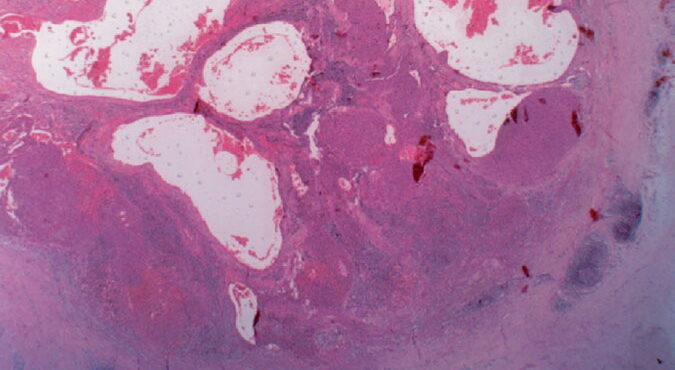

Read MoreAngiosarcoma = الساركوم الوعائي OLYMPUS DIGITAL CAMERA OLYMPUS DIGITAL CAMERA OLYMPUS DIGITAL CAMERA OLYMPUS DIGITAL CAMERA